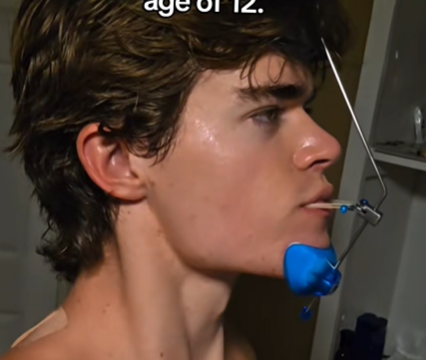

So I started treatment as a 14 yo, I had a narrow palate and a class II overjet. Now I'm 17 and still have braces (cuz I wasn't consistent tg)

Now I'm thinking I should get MARPE (or RPE), herbst, and reverse pull headgear to fix what I broke minorly. What do y'all think?

Now I'm thinking I should get MARPE (or RPE), herbst, and reverse pull headgear to fix what I broke minorly. What do y'all think?